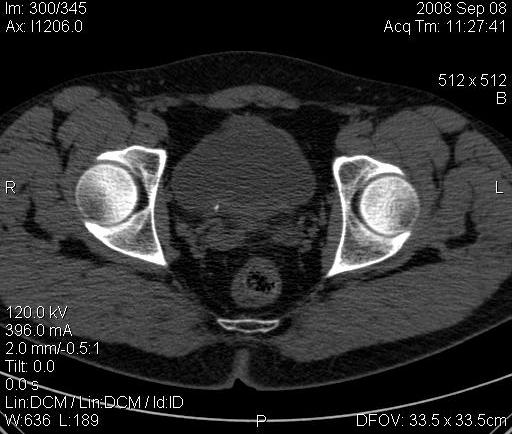

Почечная колика; на последнем аксиальном скане чётко виден мелкий (2 мм) камень в устье правого мочеточника.

Dr.Mario писал(а):Почечная колика; на последнем аксиальном скане чётко виден мелкий (2 мм) камень в устье правого мочеточника.

Для невладеющего КТ,очень четка видна аномалия на 3-4х снимках.А вот на 4-м скане в проксим.сегменте цистоида тоже есть гиперденсное точечное образование-не камень случайно?